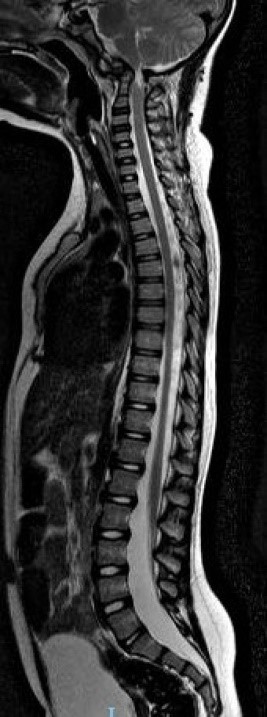

Se decide internación por síndrome medular agudo, y se realizan estudios por imágenes donde se observa lesión medular con mielomalacia debido a mal formación en charnela con inestabilidad atlanto axoidea y estrechamiento del foramen (Figuras 1, 2 y 3). En tomografía se observa agenesia del arco posterior del atlas con displasia de macizos laterales (Figura 4).

Figura 3: Resonancia columna completa preoperatorio

Figura 4: Tomografía sagital preoperatoria